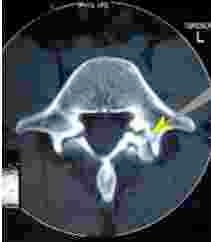

A degenerative facet joint as seen on CT scan.